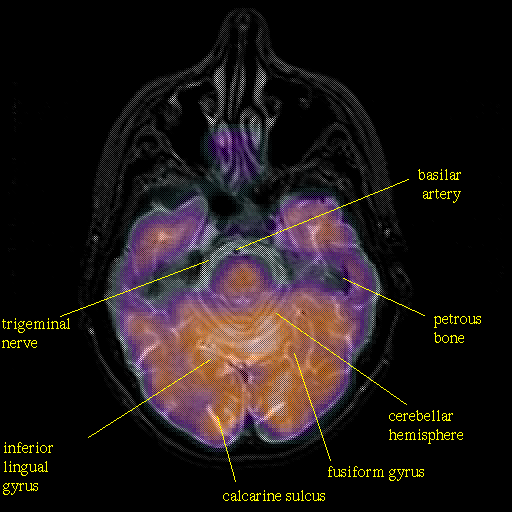

overlay: Slice 17

Slice 17

Pointers

Labeled